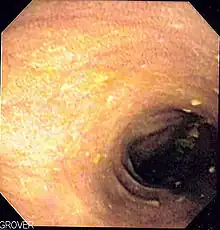

| Melanosis coli identified on colonoscopy as a brownish moiré pattern on the wall of the colon | |

Melanosis coli, also pseudomelanosis coli, is a disorder of pigmentation of the wall of the colon, often identified at the time of colonoscopy. It is benign and may have no significant correlation with disease. The brown pigment is lipofuscin in macrophages, not melanin. It is most commonly associated with the use of certain laxatives.

However, other causes are identified, including an increase in colonic epithelial apoptosis.[3] Endoscopically, the mucosa may show a brownish discoloration in a moiré pattern.